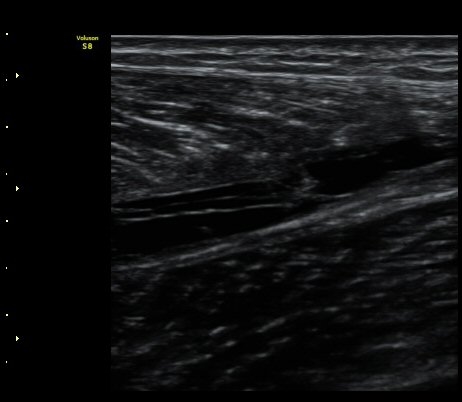

ÃÊÀ½ÆÄ °Ë»ç

¼ö»ó ÈÄ 2ÀÏ Â°

³»Ãø ºñº¹±Ù Á¾´Ü¸é°Ë»ç¿¡¼­ ±ÙÀ°°ú ÈûÁÙ ÀÌÇà ºÎÀ§¿¡ ÀÛÀº ÆÄ¿­°ú ¼ö¾× Àú·ù, ÆÄ¿­ µÈ

±ÙÀ°ÀÇ ±ÙÀ§ºÎ·Î ´ç°ÜÁüÀÌ °üÂû µÊ(±×¸² 1, 2, 3).